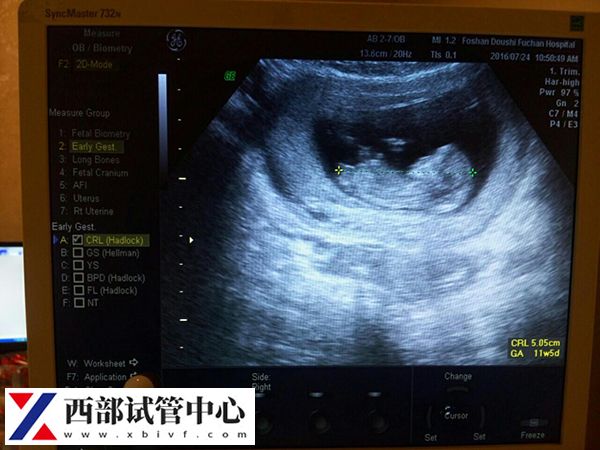

第二次超声检查

第二次B超是移植后的6-7周,检查是否有胎心的情况,再次确认单胎、双胎甚至三胎的情况,改成了解胎儿继续发育情况以调整黄体支持药物,少数情况下还有宫内宫外孕同时存在的情况。同时还要查看准妈妈宫腔内是否存在积液,如果积液较多,准妈妈就需要静养保胎,减少活动量,必要时准妈妈都有可能需要卧床保胎。